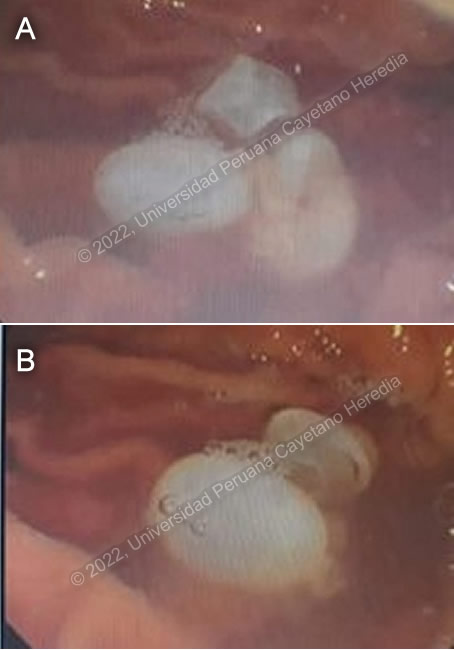

The following patient was referred to our institution for advice and further management. ![]() History: A 29-year-old male was admitted to another hospital with a 5-day history of epigastric pain radiating to the right upper quadrant, accompanied by fever and jaundice. No history of injury of trauma. Epidemiology: The patient was born in the highlands of Jauja and lived there until 16 years of age. He lived on a farm in contact with dogs and guinea pigs. The remainder of his past medical history was unremarkable. His grandmother had a space occupying lesion of the liver twenty years ago. Physical Examination: T 37.8C, pulse 85, respirations 18, BP 115/65, icteric sclera, pain on superficial palpation on the epigastrium and abdominal right upper quadrant, the rest of the examination was normal. Laboratory Results: Hb: 15 g/dL; WBC: 8670 (Neu: 5332, Eos 1483), Platelets: 247,000; Gluc: 82 mg/dL; Total bilirubin 5.6 mg/dl (direct 5.3); Alk phos 312 U/L (less than 129): GGT 387 U/L (less than 161); ALT 397 (less than 40); AST 193 (less than 40); Creatinine 1.04 mg/dl Procedures: Because of the fever, right upper quadrant abdominal pain, and jaundice, acute cholangitis was diagnosed. The patient was started on broad spectrum antibiotics and an ERCP was performed observing dilatation of the main duct (12mm) with vesicular content with white surface membranes filling the duct. Images A and B show the white vesicles exuding through an Oddi’s sphincterotomy.

Diagnosis: Echinococcus granulosus. Complicated multivesicular liver hydatid cyst with intrabiliary rupture and cholangitis.